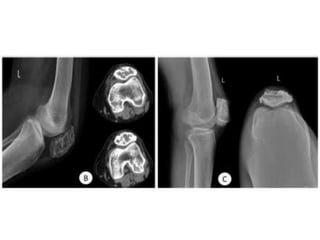

CASE 1

CASE 2

CASE 3